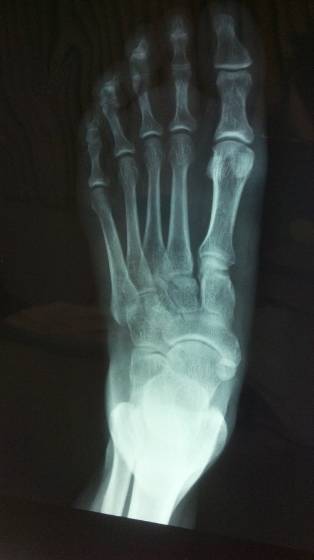

Osteonecrosis

is a disease caused by the loss of blood flow inside the bones, or ischaemia. Without blood supply, the tissue dies (necrosis) and the bone weakens.

It can be caused by a disease or serious trauma, such as a fracture or dislocation, which affects the blood supply to the bone. Other times, however, it can occur without any known cause (idiopathic osteonecrosis).

If it occurs near a joint, it can alter it and lead to the earlier onset of osteoarthritis. The bones most commonly affected include the hip, shoulder, knee, elbow, wrist, and ankle.

In the case of hip osteonecrosis

, this treatment can only be performed in cases where the femoral head still retains its spherical anatomical shape.